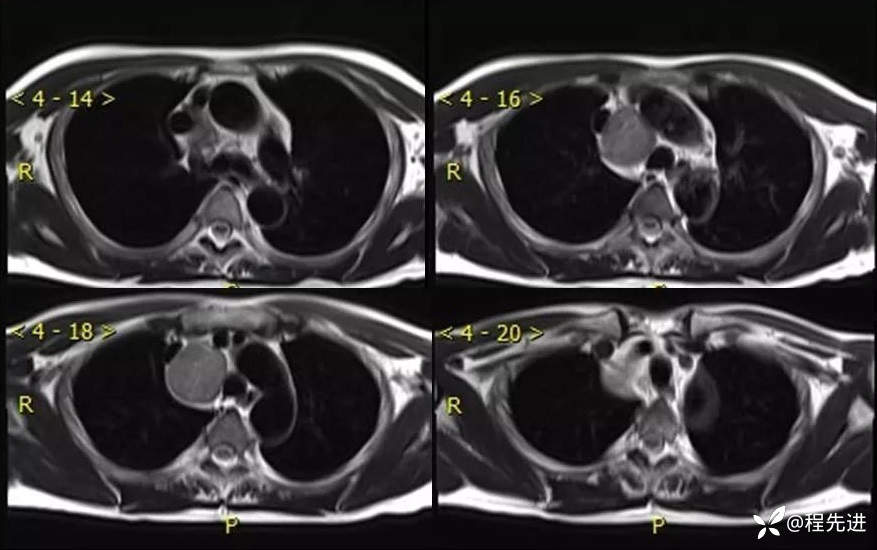

MR

T2